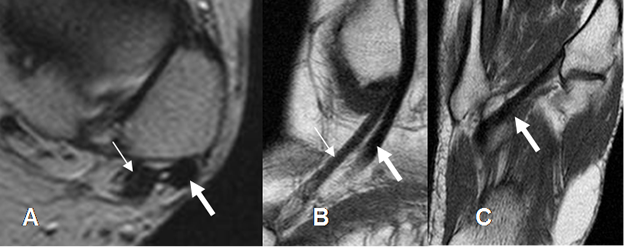

La fascia plantar se origina en la tuberosidad del calcáneo y divide en 3 ramas principales medial, central y lateral. La central se subdivide en 5 ramas, que se insertan en las falanges proximales de los dedos. Las ramas medial y lateral se insertan en las bases del 1º y 5º metatarsianos. (6). En secuencias sagitales y coronales, se aprecia como una estructura delgada e hipointensa, de 3 a 4 mm de espesor a nivel de su origen en el calcáneo. (1). (Fig 18, 19, 20 y 21).

Fig 19. Fascia plantar normal.

A y B: RM axial en T1 y C: RM coronal en T1. Rama medial (Flecha delgada), central (Flecha gruesa) y lateral (Cabeza flecha).

Fig 20. Fascia plantar normal.

A: RM sagital en T2 y B: RM sagital en STIR. Estructura hipointensa en todas las secuencias.